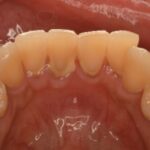

🪨 歯石とは?

プラークが唾液中のカルシウムと結合して石灰化したものです。

硬く歯にこびりつき、家庭の歯みがきでは落とせません。

歯石の表面はザラザラしており、さらにプラークが付きやすくなるという悪循環に。